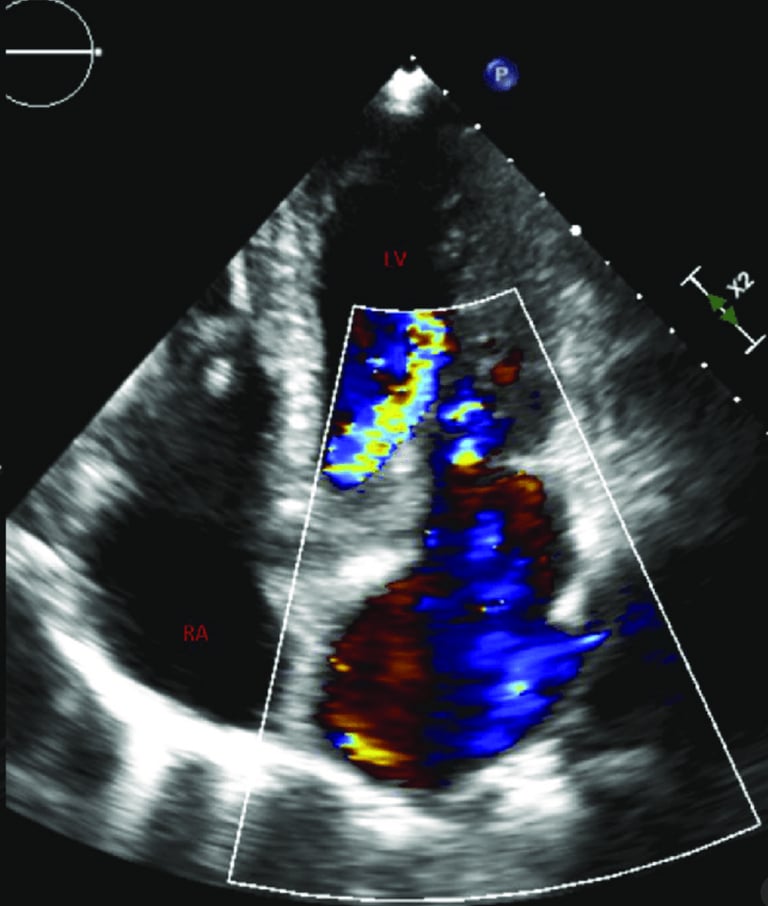

Transthoracic Echocardiogram

An echocardiogram is an ultrasound scan that uses sound waves to create detailed images of the heart, assessing its structure, function, and blood flow to diagnose various cardiac conditions.